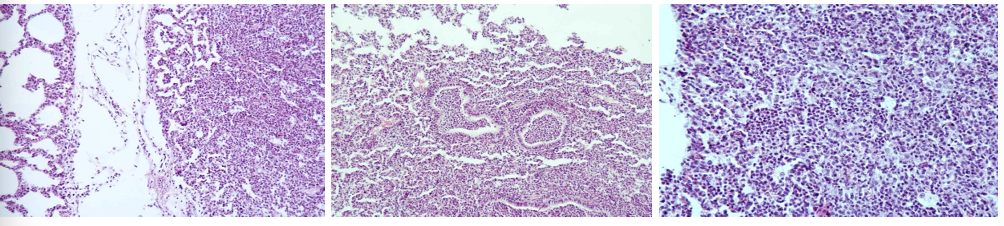

this is?

Bronchopneumonia purulenta

Description: Enlargement and engorgement of capillaries with blood and oozing of erythrocytes can be seen. Alveoli are filled with extensive infiltrate, containing different cells (leukocytes, lymphocytes, desquamated pneumocytes and macrophages, but predominantly neutrophils). Cell infiltrate lie in a blank amount of gray-pinkish homogeneous fluid exudate. Bronchial spaces are also filled with neutrophils.

Etiology: Purulent inflammation occurs when damage is more severe and large numbers of neutrophils are present. Can be caused by pyogenic bacteria such as staphylococcus, corynebacterium, streptococci (diphtheria in pigs)

Pathogenesis: Purulent inflammation is characterized by pus and large number of neutrophils. Neutrophils, pathogen or a combination of the two cause necrosis of surrounding tissue.

Pericarditis fibrinosa

Description: A layer of thickening edematous subepicaridal tissue and remnant endothelium on the surface of myocardium, covered by fibrinous mass with admixture of lymphocytes and neutrophils. Process demonstrate acute stadium of serosal fibrinous inflammation.

Etiology: Microorganisms such as diphteria, salmonella, sphaerophorus necrophorus

Pathogenesis: Fibrinous inflammation is characterized by exudate containing large amounts of fibrinogen which clots so fibrin is the most conspicuous agent. Fibrin exudation indicates severe acute vascular injury. Occur mostly on mucous and serous membranes. Fibrin can sometimes be reddened by blood and since it is chemotactic, it attracts neutrophils. In cattle, high plasma fibrinogen levels make fibrous exudate more common.